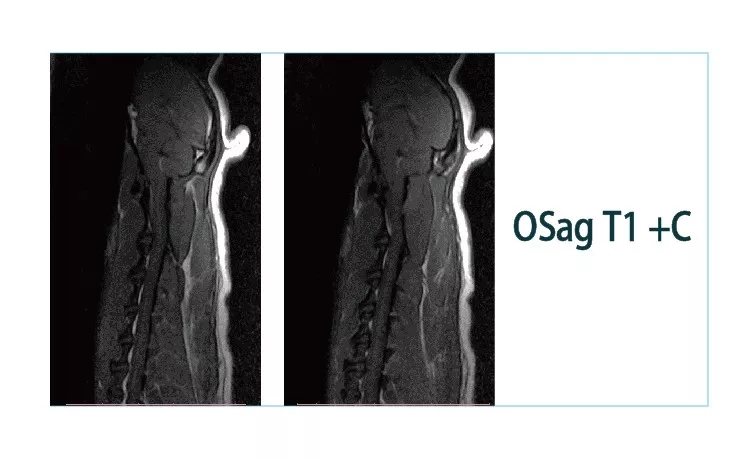

【朗润影像档案】20181221磁共振影像病例结果讨论